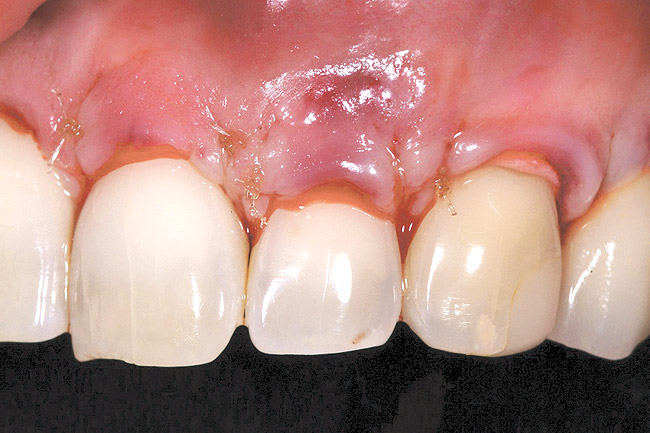

The AlloDerm material, which had been re-hydrated and enhanced with the non-activated PRP solution, was then placed into the surgical pouch with the basement membrane adjacent to the root surface (Figure 7). The dermal matrix was then secured with 6.0 polypropylene sutures (Figure 8). The graft should be positioned at the cemento-enamel junction. The pouch was then coronally advanced to cover the dermal matrix graft completely, and secured with 5.0 monocryl or 6.0 polypropylene sutures (Figure 9). The sutures were removed 1 month postoperatively; note that the need for a topical anesthetic may be necessary for patient comfort during suture removal.

The 2.5-week postoperative clinical view can be seen in Figure 10 through Figure 12. Note the rapid soft tissue healing and maturation. At 6-weeks postoperative, tissue plasty was accomplished to blend the thickened keratinized tissue, in addition to placement of class V composite restorations at teeth Nos. 5, 6, and 11 to create a new restorative margin on the root surfaces.

Figure 9  Case One Pouch coronally advanced and dermal matrix covered.

Figure 9

Figure 10  Case One The 2.5-week postoperative view, maxillary anterior.

Figure 10